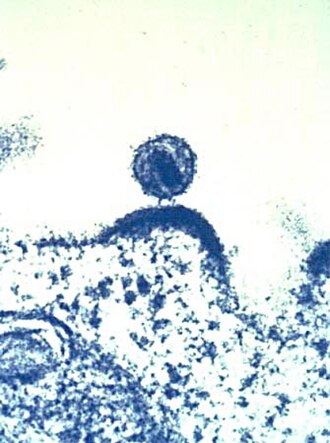

Virusi

Virusi su sičušne infektivne čestice koje se često neubrajaju u žive organizme. Oni unose svoj genski materijal (DNK) u tijelesne stanice i same se umnožavaju te tako zaraze druge stanice. Ljudske virusne infekcije jesu prehlada, ospice i HIV.